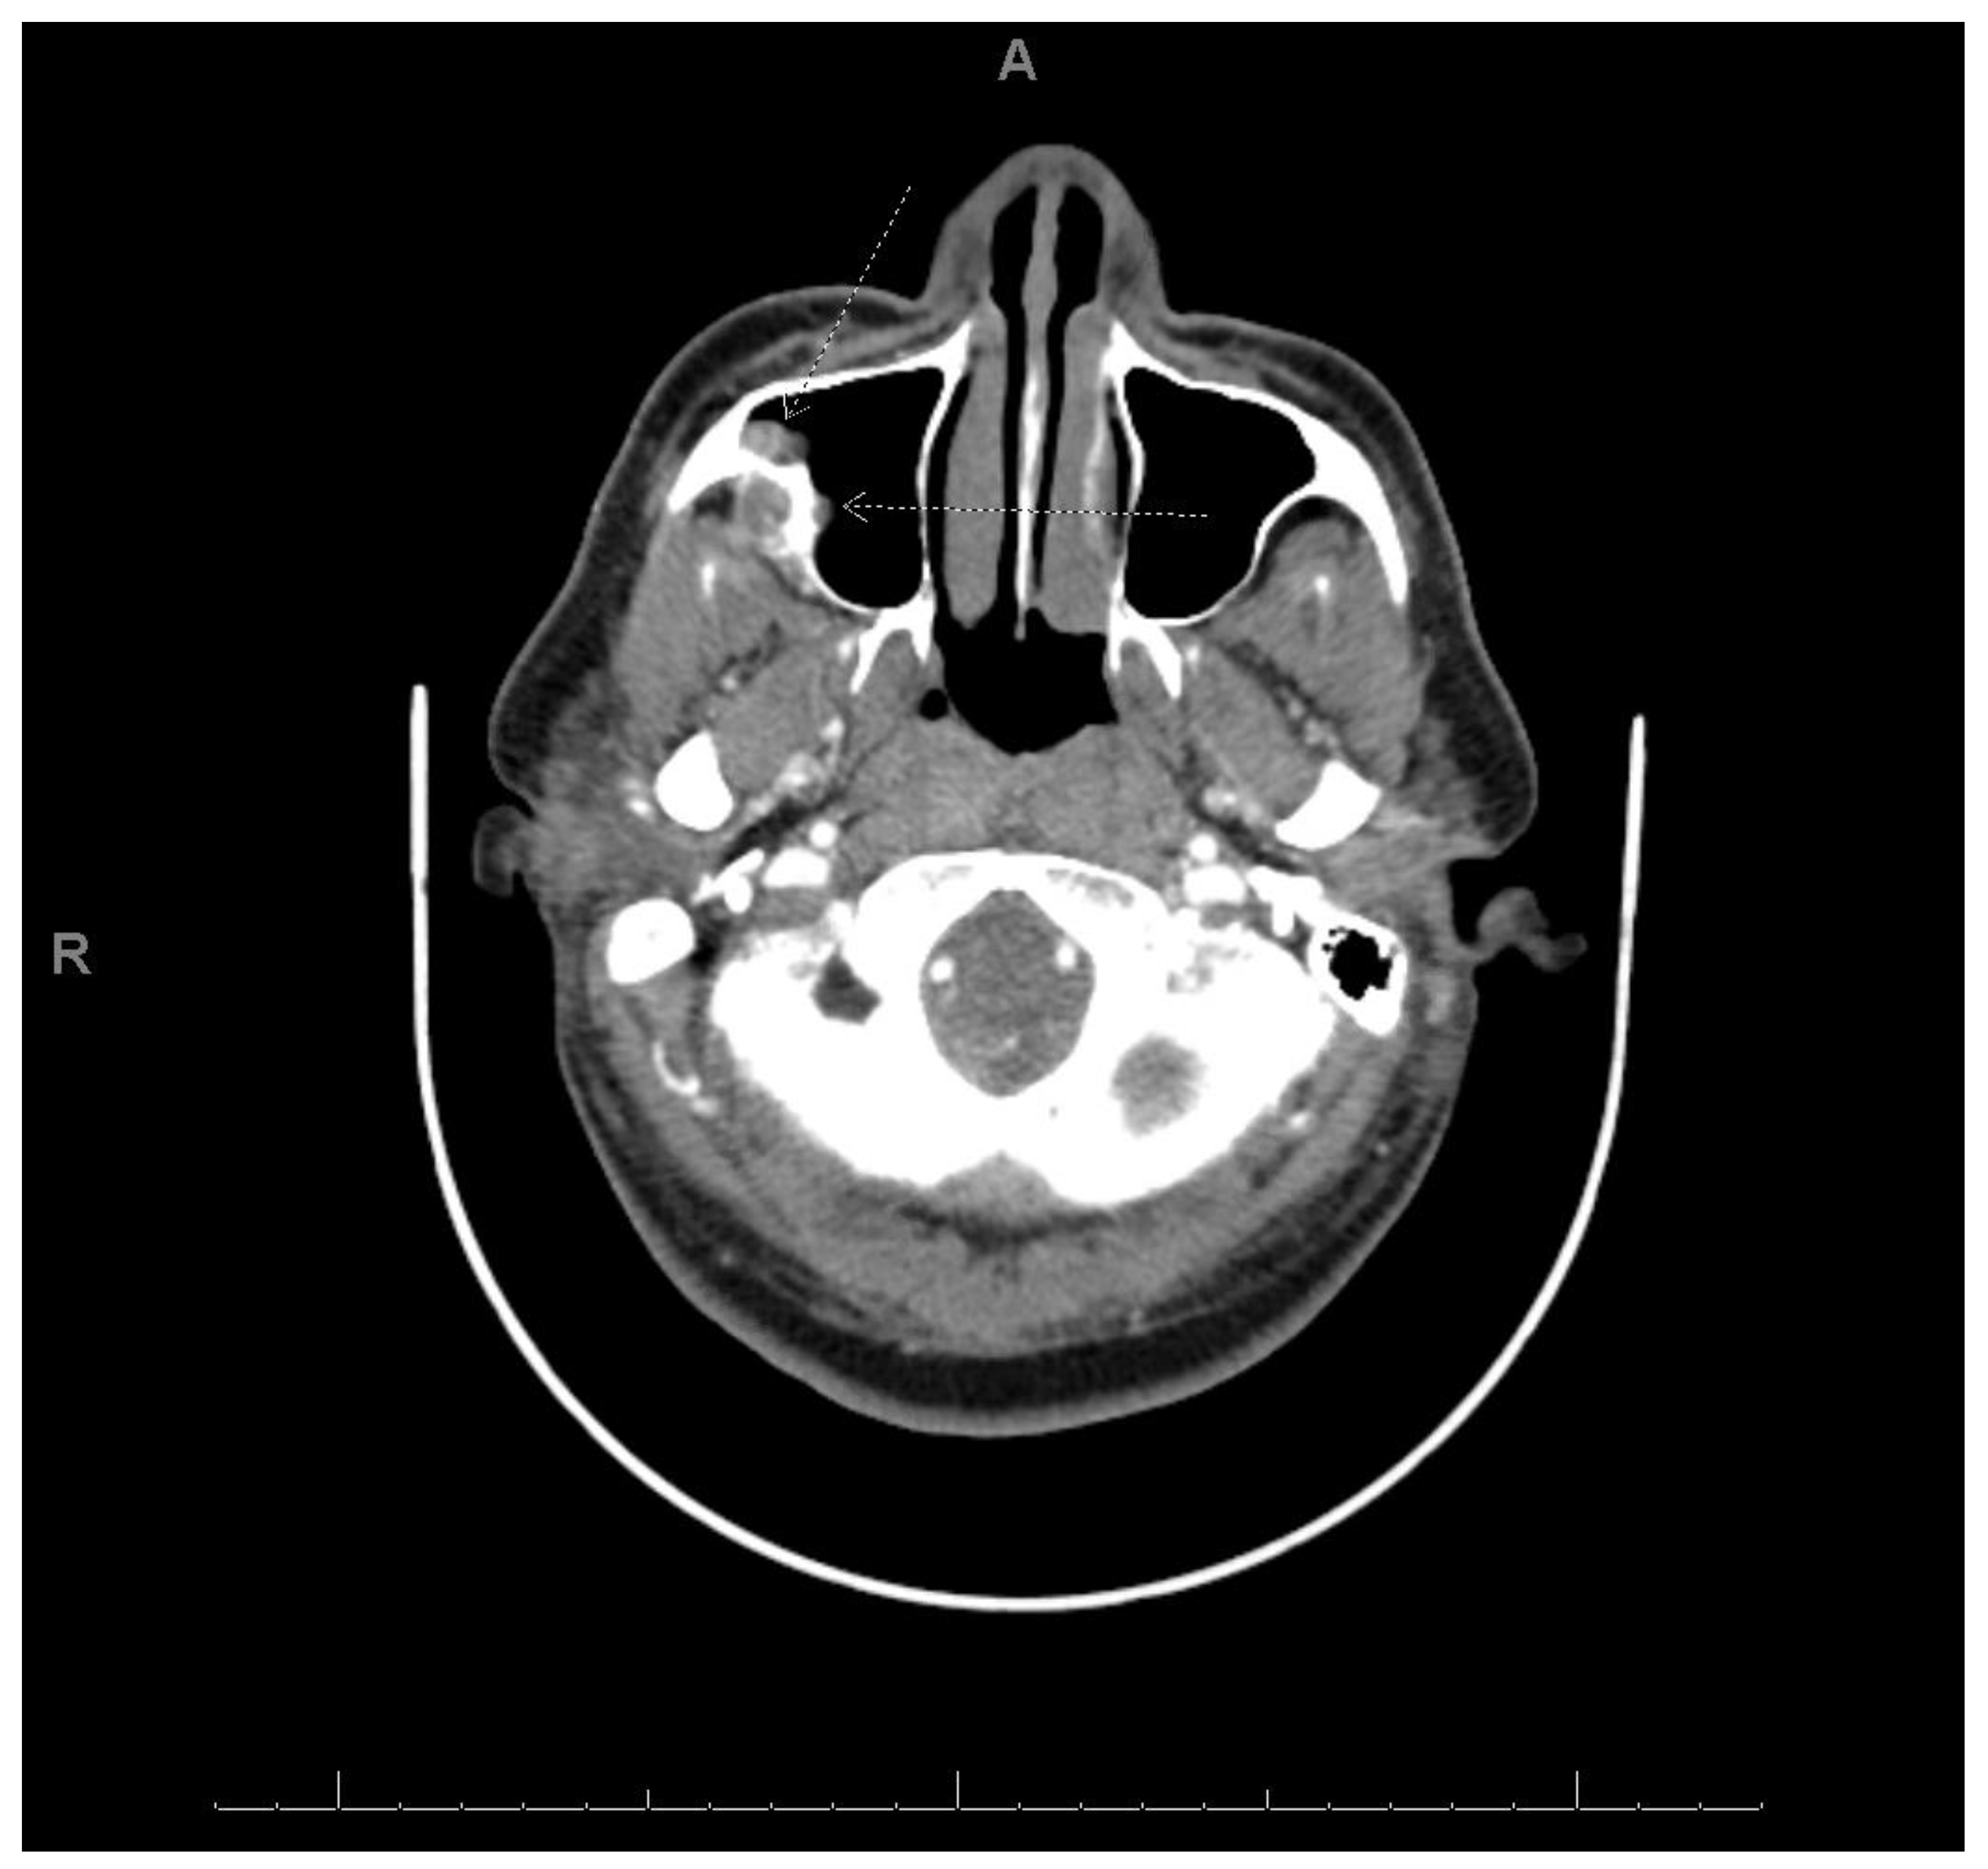

2.1. Case 1

| Location | Right maxilla | Right mandible | Right maxilla |

| Morphology | Infiltrative, non-encapsulated malignant neoplastic odontogenic epithelial proliferation with clear cell component in a dense fibrous connective tissue stroma. Neoplastic cells arranged in anastomosing trabeculae. Nuclear hyperchromasia and pleomorphism surrounded by clear, vacuolated cytoplasm. Stroma was hyalinized, densely collagenized, hypocellular, and hypovascular. | Neoplastic odontogenic epithelial proliferation diffusely infiltrated the connective tissue stroma. Neoplastic cells arranged in islands of variable size, trabeculae, and nests. Nuclei were hyperchromatic, central, and pleomorphic surrounded by clear cytoplasm. | Infiltrative odontogenic epithelial neoplasm intermixed with eosinophilic dentinoid matrix. Neoplastic cells arranged in infiltrative, non-encapsulated sheets, cords, and nests of polygonal cells with central hyperchromatic and slightly pleomorphic nuclei surrounded by clear cytoplasm and occasional pale eosinophilic cytoplasm. Occasional mitotic figures were noted. Neoplastic epithelial sheets and cords blended with eosinophilic cellular matrix without cellular rimming consistent with dentinoid deposits. |

| Procedure | Right maxillectomy with negative margins | Left mandibulectomy Right temporomandibular joint arthroplasty Left fibula free flap | Right maxillectomy without orbital exenteration Right selective neck dissection Forearm free flap Four months adjuvant radiation |